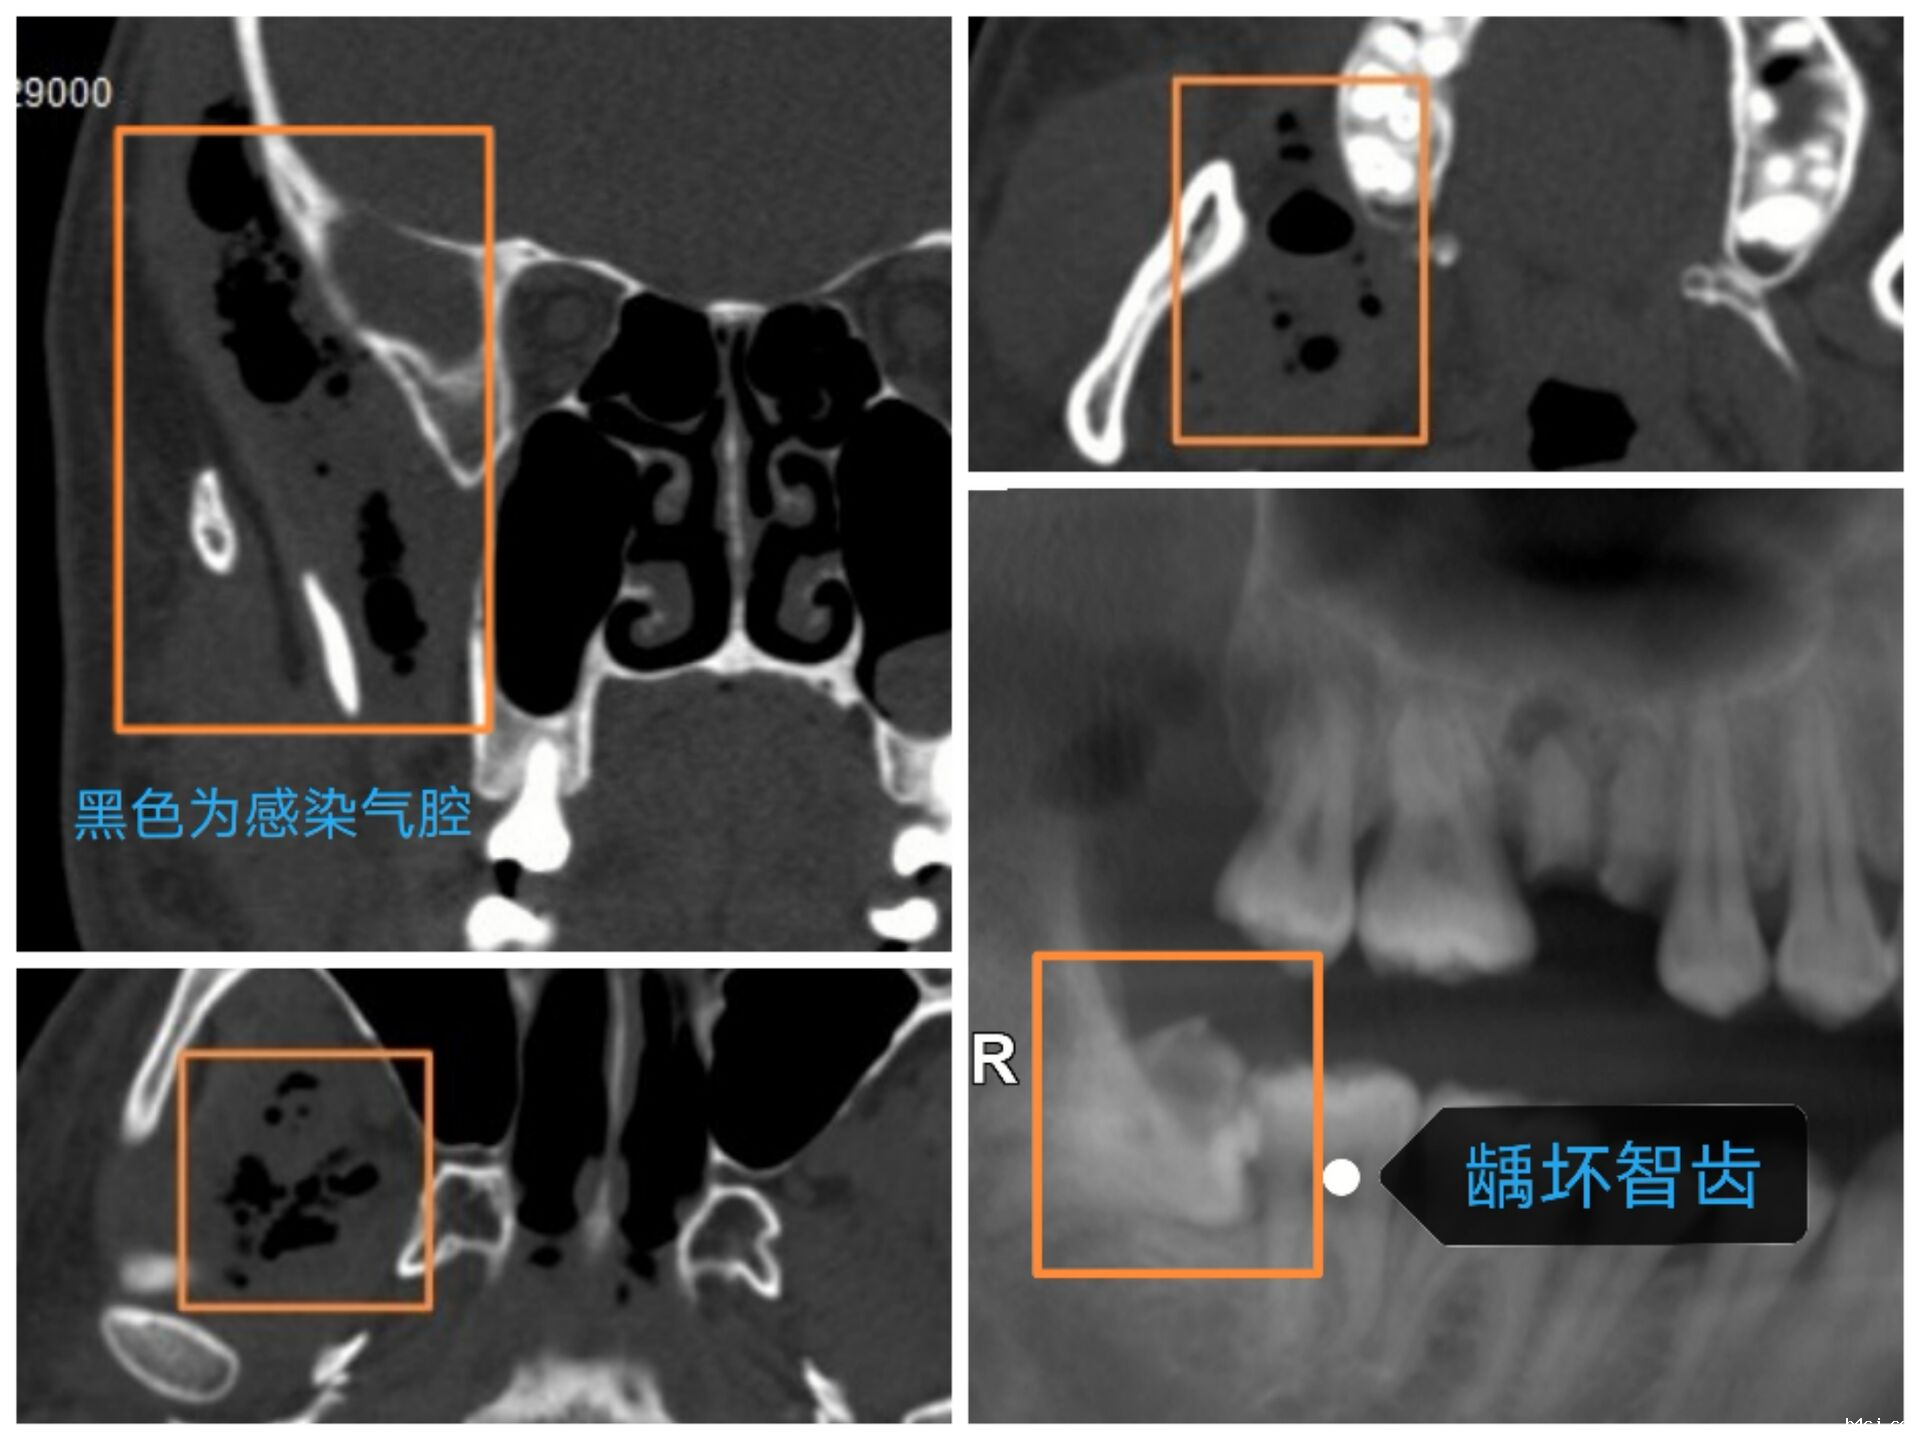

智齿容易引起感染,损害健康,甚至危及生命。如,一,冠周牙龈软组织引起的发炎。智齿萌出不全,部分牙龈覆盖,容易积存食物导致局部牙龈肿痛、化脓。这种情况尚属轻症,通过局部处理,口服抗生素即可恢复。冠周炎若治疗不及时,也有小部分会发展成邻间隙感染,此时症状严重,伴有发热、乏力等全身症状,只有通过手术才能治愈;二,龋坏智齿。细菌通过根管内牙髓组织,到达根尖区颌骨,引起感染。智齿牙根一般都比较深,尤其是牙根尖,感染继续扩散的话,就会造成颌面多间隙的感染,损害健康,危及生命。

病历二